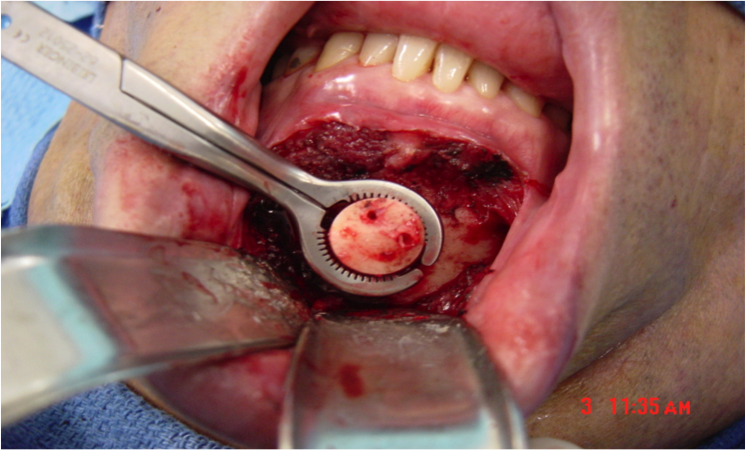

This procedure places tension on the tongue, limiting the posterior from shifting during sleep. The procedure starts with a small incision made inside the lower lip. Then, the surgeon moves away all the soft tissue to expose the lower jaw. Small rectangular cuts are then made in the lower jaw directly in front of the lower front teeth. This area attached to the genioglossus muscle is then moved forward and turned slightly. To hold this bone fragment in place, the surgeon puts in a titanium screw to immobilize it.

The photos on this website are from real surgeries performed by Dr. Ulloa. Due to the

graphic nature of the images and content, viewer discretion is advised.